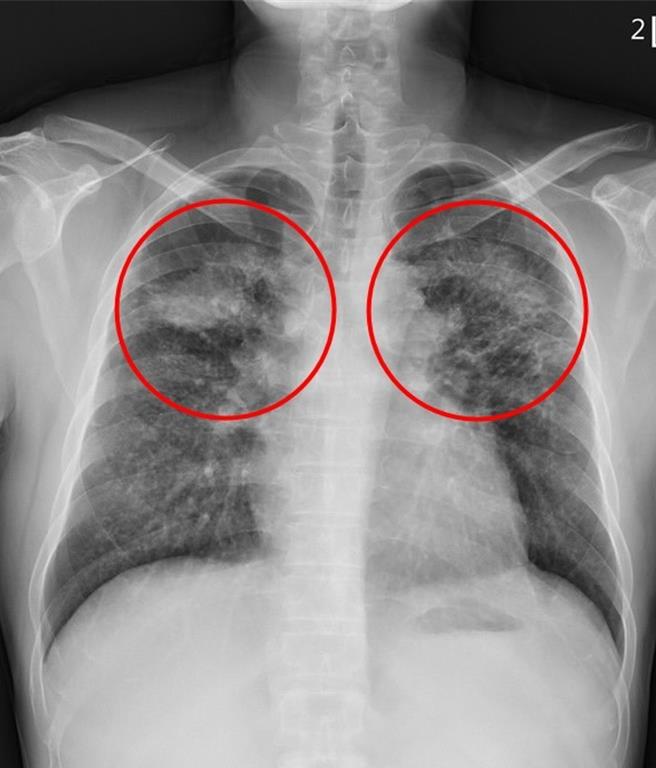

「矽肺症最可怕的是,一旦患上,不僅不可逆還將會持續惡化,且沒有特效藥」劉迪塑說,吸入的粉塵大多沉積在上肺葉,因發炎反應和局部纖維化,產生許多間質性結節,嚴重時甚至會發展為漸進性大量纖維化,在雙上肺葉形成對稱腫塊,臨床上需和惡性腫瘤或結核病的腫塊或結節做鑒別診斷。